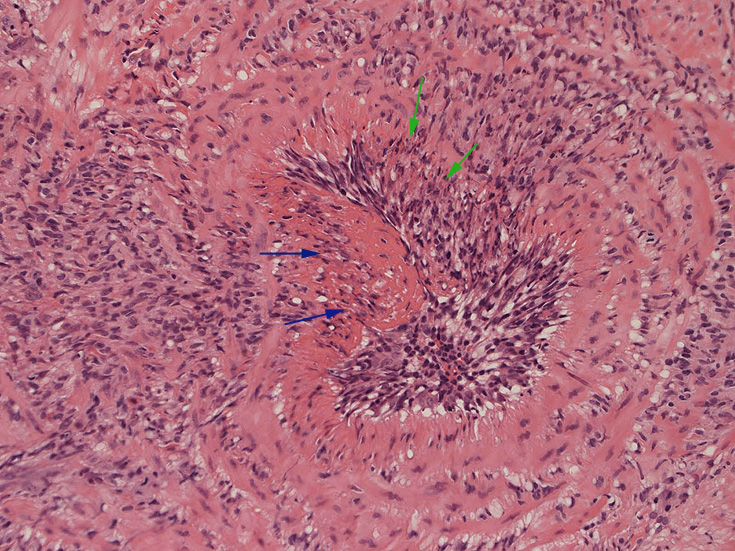

皮膚の血管(静脈・細動脈)病変、脂肪織炎 (サムネイルをクリックすると大きな画像が見られます)

fibrinoid necrosis

fibrinoid necrosis(拡大)

免疫染色:血管腔を閉塞する細胞の多くはCD68, CD163陽性細胞. CD34陽性内皮が保たれている。